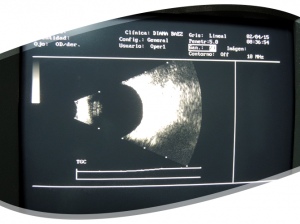

Ultrasonido

MODO A Y B

El Ultrasonido Modo A y B son métodos ultrasónicos (ecográficos), no invasivos que permiten la medición y el estudio del ojo y sus anexos